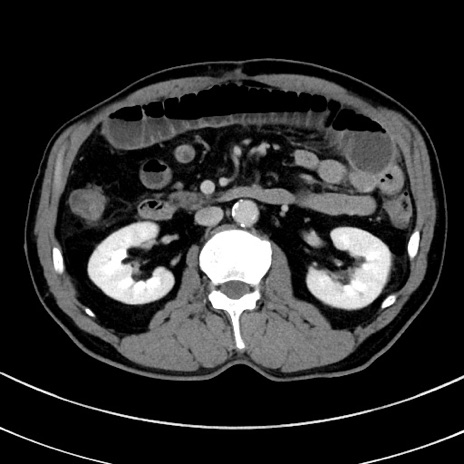

症例8(横断像)

【症例】 60歳代男性

【主訴】 黒色吐物

【現病歴】 4日前から嘔気自覚、2日前の朝食後にも嘔気あり、自分で手で嘔吐反射起こし嘔吐したところ血が混ざっていたため受診。

【既往歴】 5年前汎発性腹膜炎を伴う急性虫垂炎で手術、高血圧、前立腺肥大症、高脂血症

【身体所見】 腹部正中に手術癩痕あり 腹部平坦・軟圧痛なし膨満感あり

【データ】WBC 8400、CRP 4.54